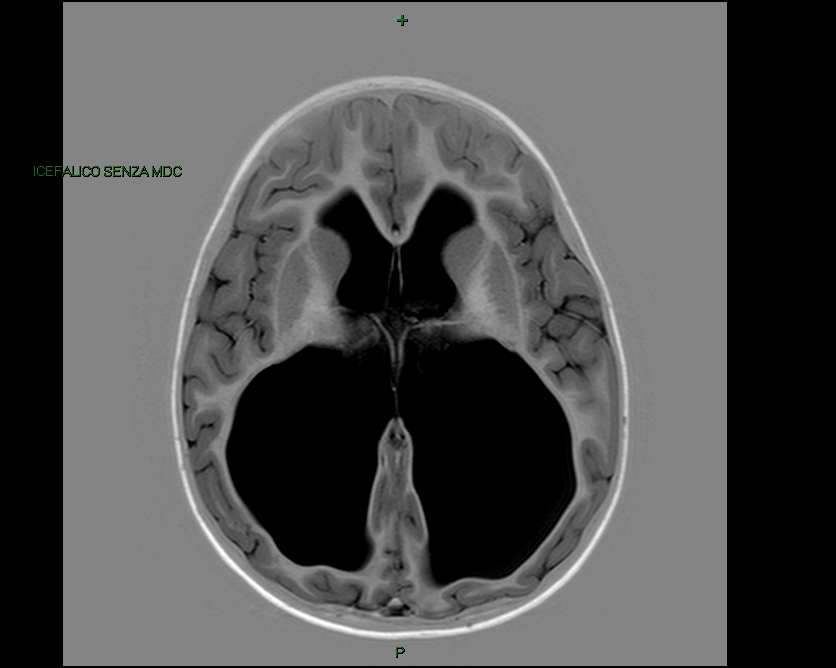

Eseguiamo finalmente la tanto attesa RMN che mostra: �idrocefalo tetraventricolare di grado severo e cisti liquorale retro e sottovermiana compatibile con tasca di Blake persistente. Non segni di ipertensione endocranica� (Figura 1 e Figura 2). Dopo aver escluso cause infettive (in particolare la ricerca di CMV DNA � negativa) e aver eseguito l�esame del fundus oculi che rileva papille pallide a limiti netti (con potenziali evocati visivi nella norma), confermiamo la diagnosi malformativa.

Figura 2. Idrocefalo in sezione trasversale (RMN pre-intervento)